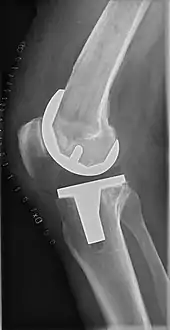

Knee replacement is routinely evaluated by X-ray, including the following measures:

- FFC: frontal femoral component angle. It is typically regarded as optimal when being 2–7° in valgus.[61]

- FTC: frontal tibial component angle, which is regarded as optimal when being at a right angle. A varus position of more than 3° has generally been found to increase the failure rate of the prosthesis.[61]

- Anterior femoral notching (the femoral component causing reduced thickness of the distal femur anteriorly), seems to cause an increased risk of fractures when exceeding about 3 mm.[62]

- LTC: lateral (or sagittal) tibial component angle, which is ideally positioned so that the tibia is 0–7° flexed compared to at a right angle with the tibial plate.[61]